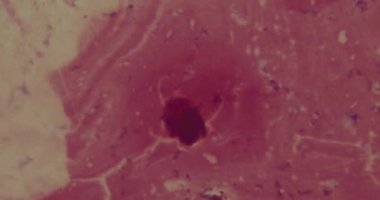

Hareketli bir 8 mm film liderinin ayrıntılı görünümü belirgin bir kırmızı dikey çizgi ve bir ışık arkaplanı karşısında saat yönünün tersine dönen metni gösterir